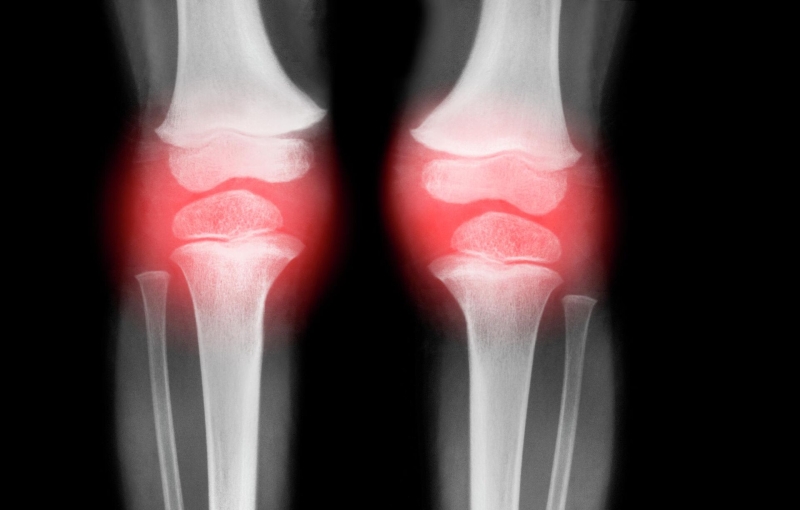

Период болей и беспокойства в суставах может длиться от нескольких месяцев до нескольких лет.

Боль в коленях

Также ввиду поражения суставов у инфицированных чикунгуньей после выздоровления может длительно сохраняться малая подвижность суставов и боли в них.

УЗИ суставов при данном заболевании обычно проводят с целью выявить в них наличие воспалительных изменений, что является частым побочным эффектом.